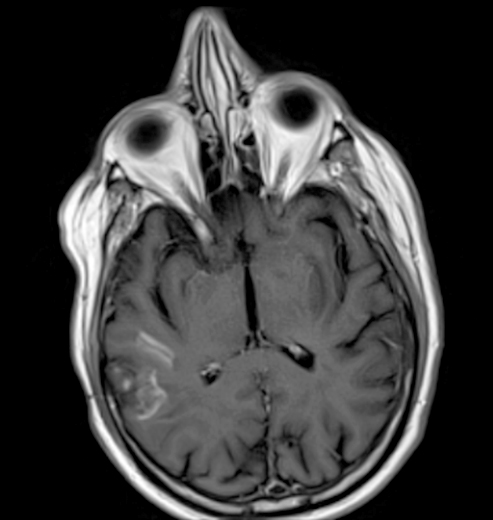

Radiology description

- CT unenhanced

- Early / acute signs: loss of definition between gray and white matter, cortical hypoattenuation and effacement of the sulci (Radiology 2005;235:444)

- Loss of the insular cortex in acute middle cerebral artery (MCA) infarcts (Radiology 1990;176:801)

- Hyperdensity of the MCA (i.e., hyperdense artery sign) is observed in 30 - 40% of patients with acute MCA infarcts (Stroke 1992;23:317)

- Chronic infarcts show cavitation sometimes with mineralization

- MRI

- Diffusion weighted imaging (DWI): hyperintense signal in the acutely infarcted tissue; low signal on apparent diffusion coefficient (ADC) map

- Infarcts are often T2 hyperintense

- Collateral flow on FLAIR: linear or serpentine hyperintensities distal to the site of obstruction (Neurology 2009;72:1134)

- Perfusion weighted imaging (PWI) - DWI mismatch: used to estimate the salvageable tissue (i.e., penumbra) in acute infarct (Neuroimaging Clin N Am 2021;31:177, AJNR Am J Neuroradiol 2015;36:32)

- Ischemic areas on PWI are compared with areas shown by DWI (i.e., the infarct core or nonsalvageable tissue); the mismatch represents the volume of salvageable tissue with reperfusion therapy

- Chronic infarcts show absence of contrast enhancement in strokes older than 4 months (Radiographics 2012;32:1285)

Radiology images